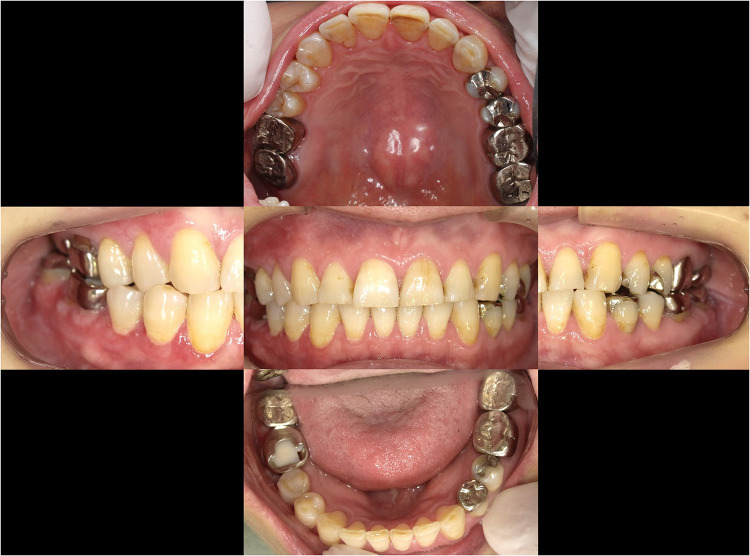

Patients and methods: A 55-year-old female presented with redness and pain near the buccal gingiva of the right mandibular first molar, along with white lace-like patches. Intraoral examination revealed multiple metal restorations, and element analysis identified Zn and Co in several crowns. Based on these findings, a metal allergy was diagnosed. All metal crowns were replaced with zirconia. However, symptoms persisted. A biopsy later confirmed OLP, and steroid therapy was initiated.

Results: Despite removal of the suspected allergenic metals, the inflammation did not resolve, suggesting metal allergy was not the primary cause. Subsequent treatment with steroids led to gradual resolution, supporting the diagnosis of OLP as the primary condition.